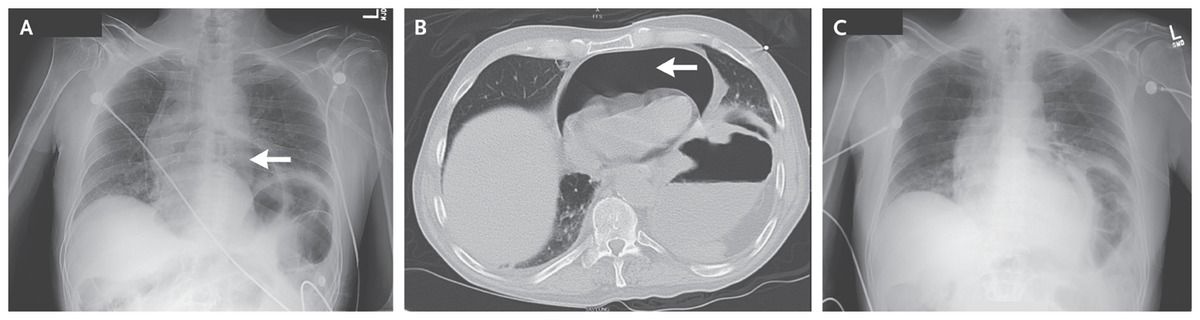

Chest radiography showed air in the pericardium (Panel A, arrow). Computed tomography of the chest confirmed the presence of a large pneumopericardium (Panel B, arrow) but no pneumothorax or pneumoperitoneum.

Emergency pericardiocentesis was performed, and a large amount of air was aspirated. The patient’s vital signs immediately stabilized. Repeat chest radiography showed improvement of the pneumopericardium (Panel C).